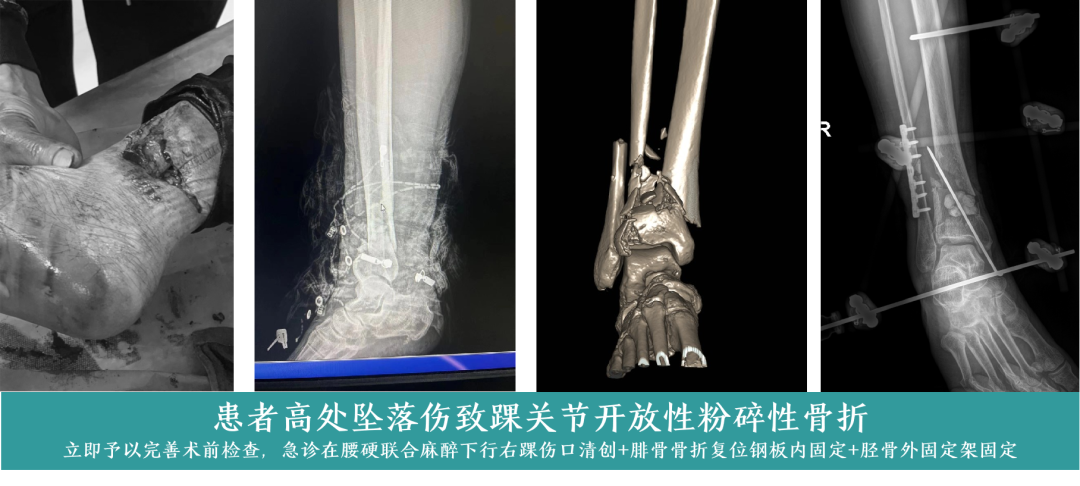

03 开放性粉碎性骨折

开放性粉碎性骨折病情严重,治疗难度大,易出现感染、愈合不良等并发症。科室凭借先进的诊疗设备和精湛的手术技术,在清创、复位、固定等环节精准操作,结合术后科学的康复指导,有效提高治疗成功率,帮助患者最大限度恢复肢体功能。